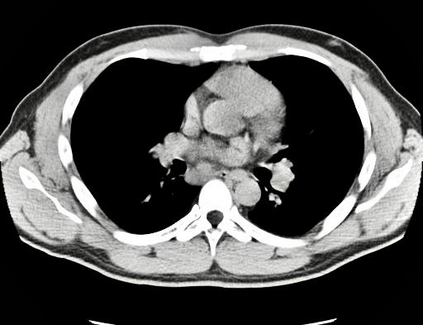

The evaluation of infectious disease processes on radiologic images is an important and challenging task in medical image analysis. Pulmonary infections can often be best imaged and evaluated through computed tomography (CT) scans, which are often not available in low-resource environments and difficult to obtain for critically ill patients. On the other hand, X-ray, a different type of imaging procedure, is inexpensive, often available at the bedside and more widely available, but offers a simpler, two dimensional image. We show that by relying on a model that learns to generate CT images from X-rays synthetically, we can improve the automatic disease classification accuracy and provide clinicians with a different look at the pulmonary disease process. Specifically, we investigate Tuberculosis (TB), a deadly bacterial infectious disease that predominantly affects the lungs, but also other organ systems. We show that relying on synthetically generated CT improves TB identification by 7.50% and distinguishes TB properties up to 12.16% better than the X-ray baseline.